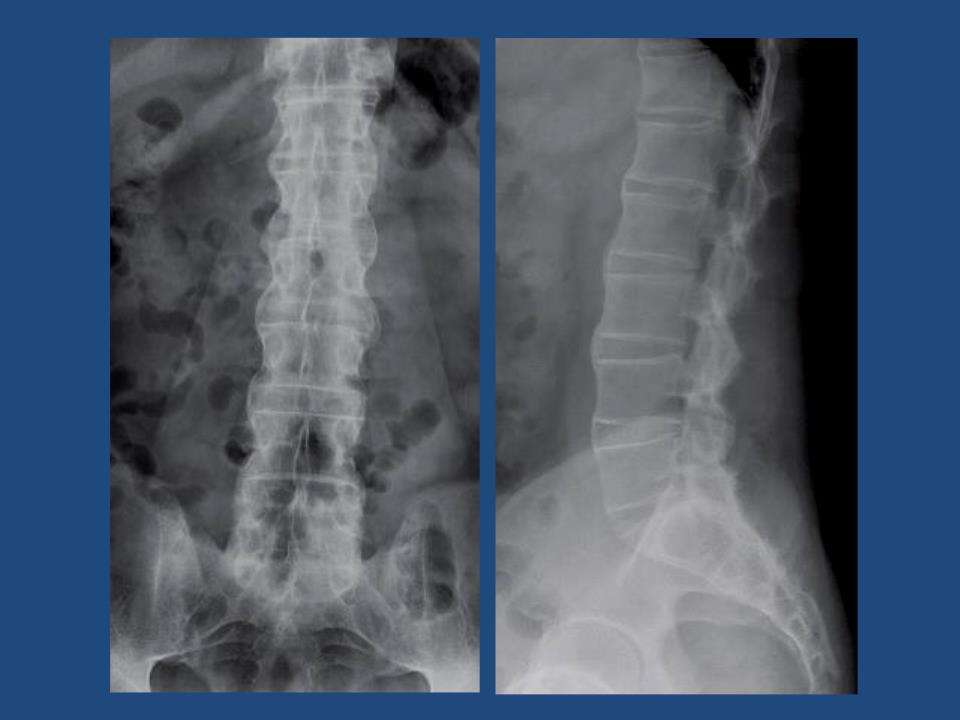

强直性脊柱炎的英文简称为AS,我们可以又把它叫做类风湿性脊柱炎 ...